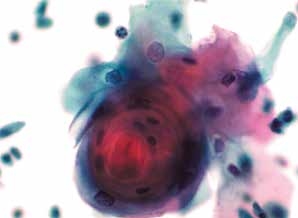

图4-51 角化型鳞癌(中倍、液基、巴氏染色)

肿瘤素质:坏死性碎片、纤维蛋白及陈旧性出血。HSIL的背景相对干净,鳞癌常伴有肿瘤素质。

图4-52 角化型鳞癌(高倍、液基、巴氏染色)

癌性角化珠,细胞异型性明显,角化型鳞状细胞癌可见此癌性角化珠。